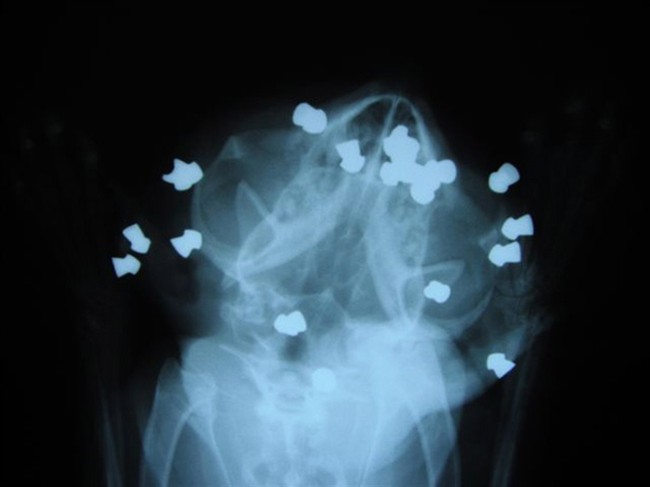

An x-ray of a cat which was shot with a pellet gun is shown in a handout photo.

An x-ray of a cat which was shot with a pellet gun is shown in a handout photo. THE CANADIAN PRESS/Sarnia Humane Society

SARNIA, Ont. – Police say they have made an arrest in an animal cruelty case involving a cat found in a southwestern Ontario community suffering from as many as 17 pellet wounds to his head.

The Sarnia and District Humane Society says Joe is now on the mend after having surgery to remove the pellets, but that the cat lost an eye due to his injuries.